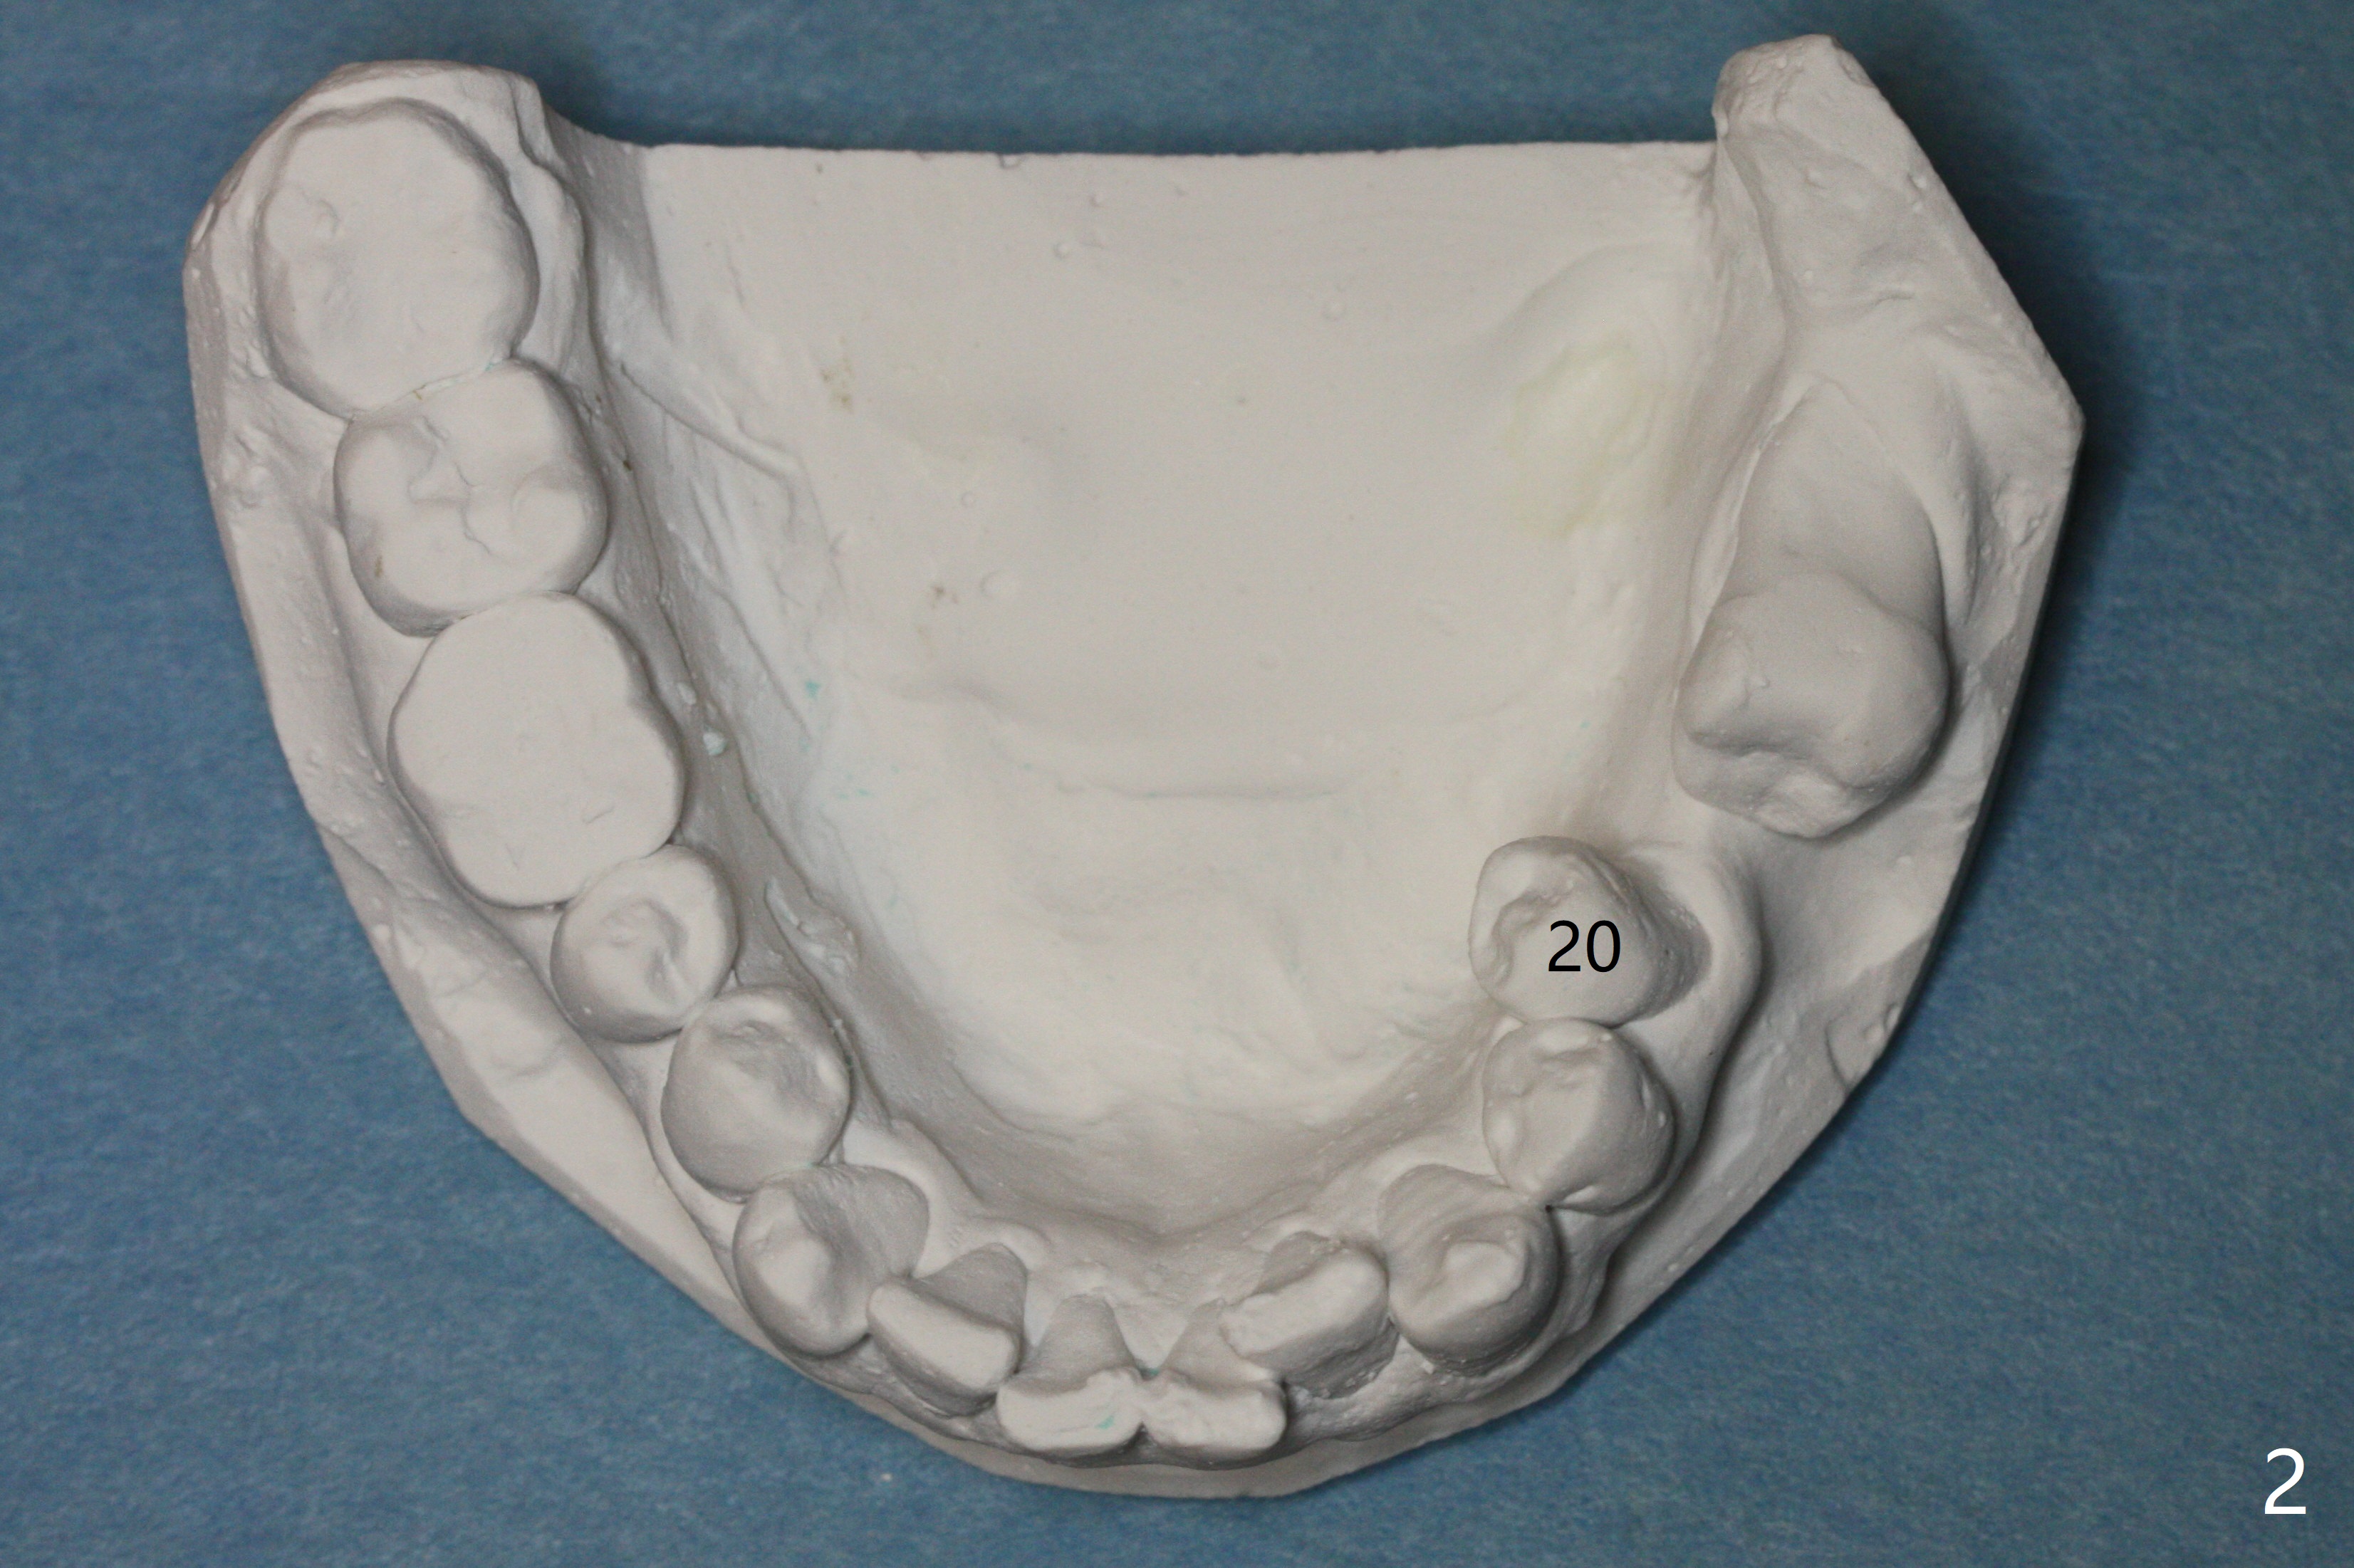

A 43-year-old man has poor dentition on the left: 1st molar missing, 2nd molar mesial inclination (Fig.1) and 2nd bicuspid lingual tilt (Fig.2). The latter is nonfunctional (Fig.3 (linguoposterior view). Two molar implants will be placed in a position so that their crowns will be in cross bite (Fig.4,5), the same occlusal scheme as the teeth #21 and 22. When these implants osteointegrate, the provisional crowns (Fig.6 P) will be supraocclusal so that there is clearance (*) for #20 to upright orthodontically (Fig.7-9). Moreover, these implants will be used anchorage as well as #21 and 22. Panoramic X-ray (Fig.1) and CBCT (Fig.10-12) show limited bone height at the sites of #18 and 19. It appears that 5x8 and 5.9x6 mm implants are appropriate with ridge reduction at #19.